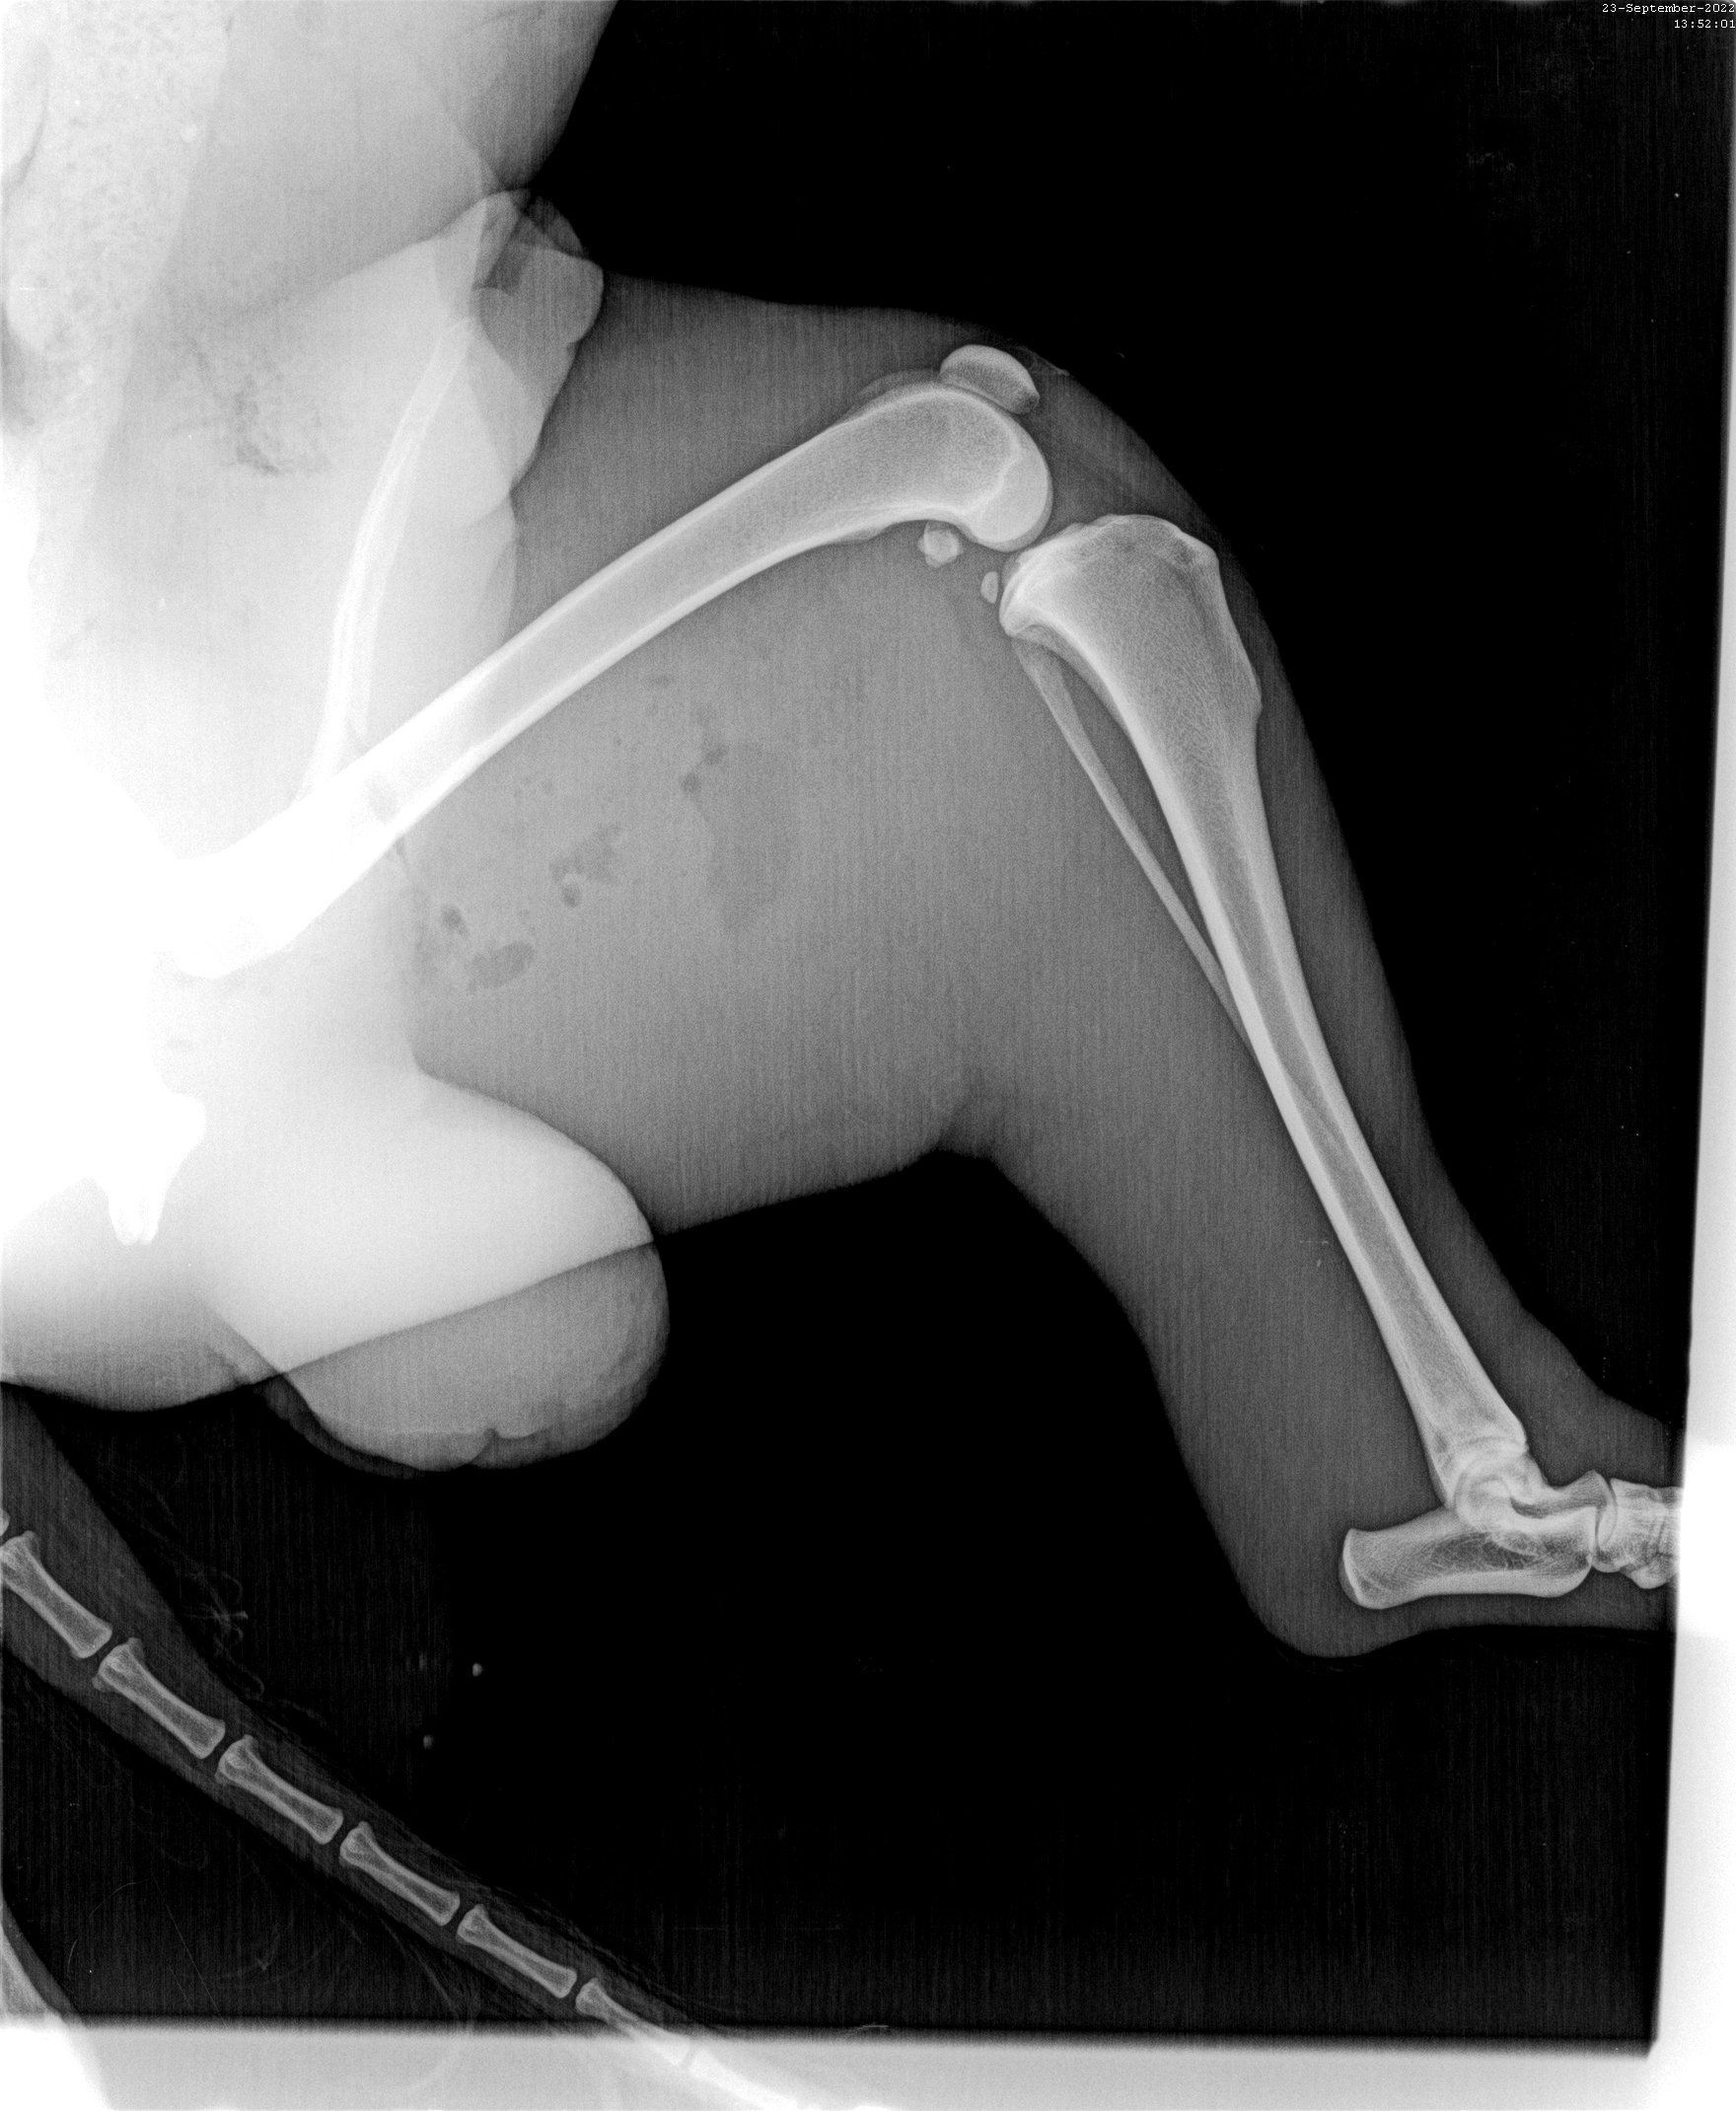

Der Klinikbericht zu der kleinen blinden Hündin ist da:

VETERINARY CLINIC Thessaloniki

„REPORT" Der Hund namens Nike wurde am 21/09/2022 mit neurologischen Symptomen vorgestellt: Ataxie, Desorientierung, Muskelzittern und unsicherer Gang. Nach der neurologischen Untersuchung wurde eine Erkrankung des Vorderhirns vermutet. Die Blutuntersuchung war innerhalb normaler Grenzen. Die Liquor-Analyse ergab keinen Hinweis auf eine Infektionskrankheit oder eine auf Steroide ansprechende Meningoenzephalitis. Es wird ein MRT des Gehirns und eine neurologische Untersuchung durch einen Facharzt für Neurologie empfohlen, um eine angeborene Hirnerkrankung zu bestätigen und die Prognose zu bestätigen. Die Untersuchungen von Nike sind beigefügt (s.Bilder)“

Diese Untersuchung (MRT) würden wir gern machen lassen, denn Nike hat ein Recht zu leben. Nur so können wir sie optimal fördern. Wir suchen also Paten, die mit uns für die kleine Kämpferin sorgen wollen. Bitte helft Nike!!!

Kilian - Opfer eines Rücksichtslosen

Angefahren und liegen gelassen worden ist dieser Rüde von Aliki auf dem Weg nach Kavala am Straßenrand gefunden worden. Zusammen mit Richarda ist Kilian ins Krankenhaus gebracht worden wo zuerst einmal die Wunden gereinigt wurden, mehrere offene Wunden mussten genäht werden, ein Beinbruch ist offensichtlich, doch das Röntgengerät war kaputt, so dass hier erst später Genaueres gesagt werden kann. Dieser hübsche Settermix litt unendlich, hoffen wir, dass unsere Hilfe ausreichen wird.

Update zu Kilian🐕

Dieser Setter-Mix, der den treffenden Namen Kilian erhalten hat - er braucht wirklich einen Schutzengel- ist direkt zum Arzt gebracht worden, der zuerst einmal sämtliche offenen Wunden desinfiziert hat und damit den ersten Heilprozess angestoßen hat. Nun war das Röntgen-Gerät defekt, weshalb er nun erneut zu einer Klinik gebracht werden musste, um seine Hüfte zu röntgen, da bei dem Autounfall vermutlich nicht nur diese fürchterlichen äußeren Wunden zurückblieben. Kilian verhält sich sehr tapfer, hoffen wir, dass die Hilfe, die er in Griechenland erhält, auch von Deutschland aus weiter unterstützt wird. 💕Wer mit einer (einmaligen oder monatlichen) Spende Pate dieses Unfallopfers werden möchte, kann dies über folgenden Link! 💙